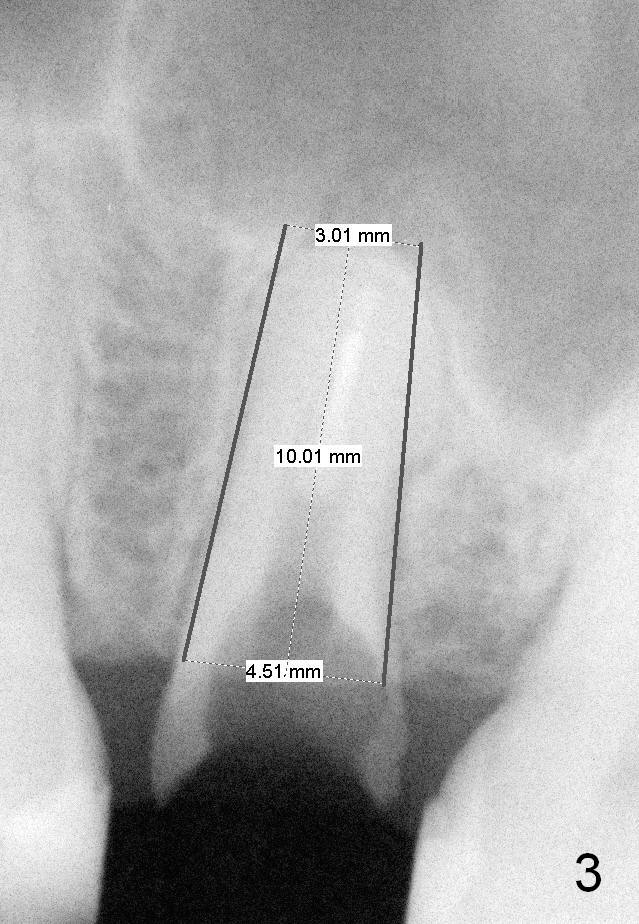

A 40-year-old lady has multiple restorations (Fig.1). The crown has dislodged from the tooth #13 twice in the last 2 years (Fig.2). When the tooth is extracted, a 4.5x10 mm bone level or 4.5x14 mm tissue level implant will be placed immediately with sinus lift (Fig.3).